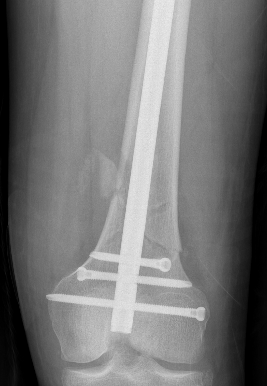

Type C: Complete articular

Xray / CT

Dual Plate

Indications

Significant comminution

Loss of medial cortical buttress

Technique

Results

- 21 comminuted distal femur fractures

- increased union rates with double v single plate

- increased revision rate with single plate